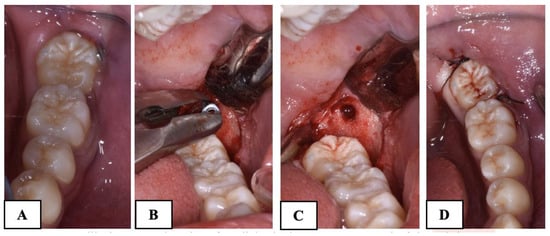

For the subjects treated with the traditional brass wire technique (Group A), follow-up visits were scheduled every 20 days, during which wire activations were performed until the uprighting of the MM2 was complete. In contrast, the Group B subjects had monthly follow-up visits until the complete uprighting of the MM2. The difference in the follow-up between the two groups is due to the need to periodically activate the brass wire to ensure the continuous movement of the MM2. In Group B, a longer follow-up was implemented because it was not necessary to reactivate the elastic chain. However, it remained important to monitor the patient for any potential complications, such as mini-implant failure or the detachment of the orthodontic button. In all cases treated with skeletal anchorage, there was no need to replace or reactivate the elastic chain, significantly reducing discomfort for the subjects. No miniscrew stability issues were observed in the Group B participants. The treatment was considered completed when the mesial marginal ridge of MM2 had passed the point of contact with the distal marginal ridge of MM1. The treatment time was recorded. A radiographic control was made before removing the orthodontic appliance in both groups (Figure 4). The advantages and disadvantages of the two techniques are shown in Table 1.

The brass wire, miniscrew, and orthodontic brackets were removed at the end of the treatment (Figure 5).

Figure 4. Pre-treatment (A) and post-treatment (B) X-ray of Group A subjects treated with brass wire; pre-treatment (C) and post-treatment (D) X-ray of Group B subjects treated with skeletal anchorage.

Figure 5. (A): Mandibular second molar after disimpaction; (B,C): removal of the miniscrew; (D): suture.